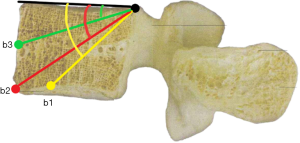

To investigate fully radiographic anatomy of PETOFPC, the authors chose to measure the distances from the posterior corner (P point, Figure 1) in lumbar spine to the corresponding targets.

Posterior corner in lumbar spine was selected as the screw entry point (P point) for oblique fixation. The screw entry point (P point) in posterior-inferior corner is the bony area between the upper margin of the pedicle and the upper endplate. The screw entry point (P point) in posterior-superior corner is the bony area between the lower margin of the pedicle and the lower endplate (Figure 2). The corresponding targets are A, B, C, D, E, and F, respectively (A: the middle point of the contralateral anterior-middle 1/3, B: the contralateral anterior-middle point, C: the middle point of the contralateral side, D: the upper point of contralateral anterior-middle 1/3, E: the contralateral anterior-upper point, F: the middle-upper point of the contralateral side) in the contralateral anterior region (Figure 3).

b1: the angle between the line, which is from the posterior-upper corner of the lower vertebral body to front-middle 1/3 of the lower endplate, and upper endplate parallel line.

b2: the angle between the line, which is from the posterior-upper corner of the lower vertebral body to anterior-lower corner, and upper endplate parallel line.

b3: the angle between the line, which is from the posterior-upper corner of the lower vertebral body to the midpoint of the anterior border, and upper endplate parallel line.

a1: the angle between the line, which is from the posterior-lower corner of the upper vertebral body to front-middle 1/3 of the upper endplate, and lower endplate parallel line.

a2: the angle between the line, which is from the posterior-lower corner of the upper vertebral body to anterior-upper corner, and lower endplate parallel line.

a3: the angle between the line, which is from the posterior-lower corner of the upper vertebral body to the midpoint of the anterior border, and lower endplate parallel line.